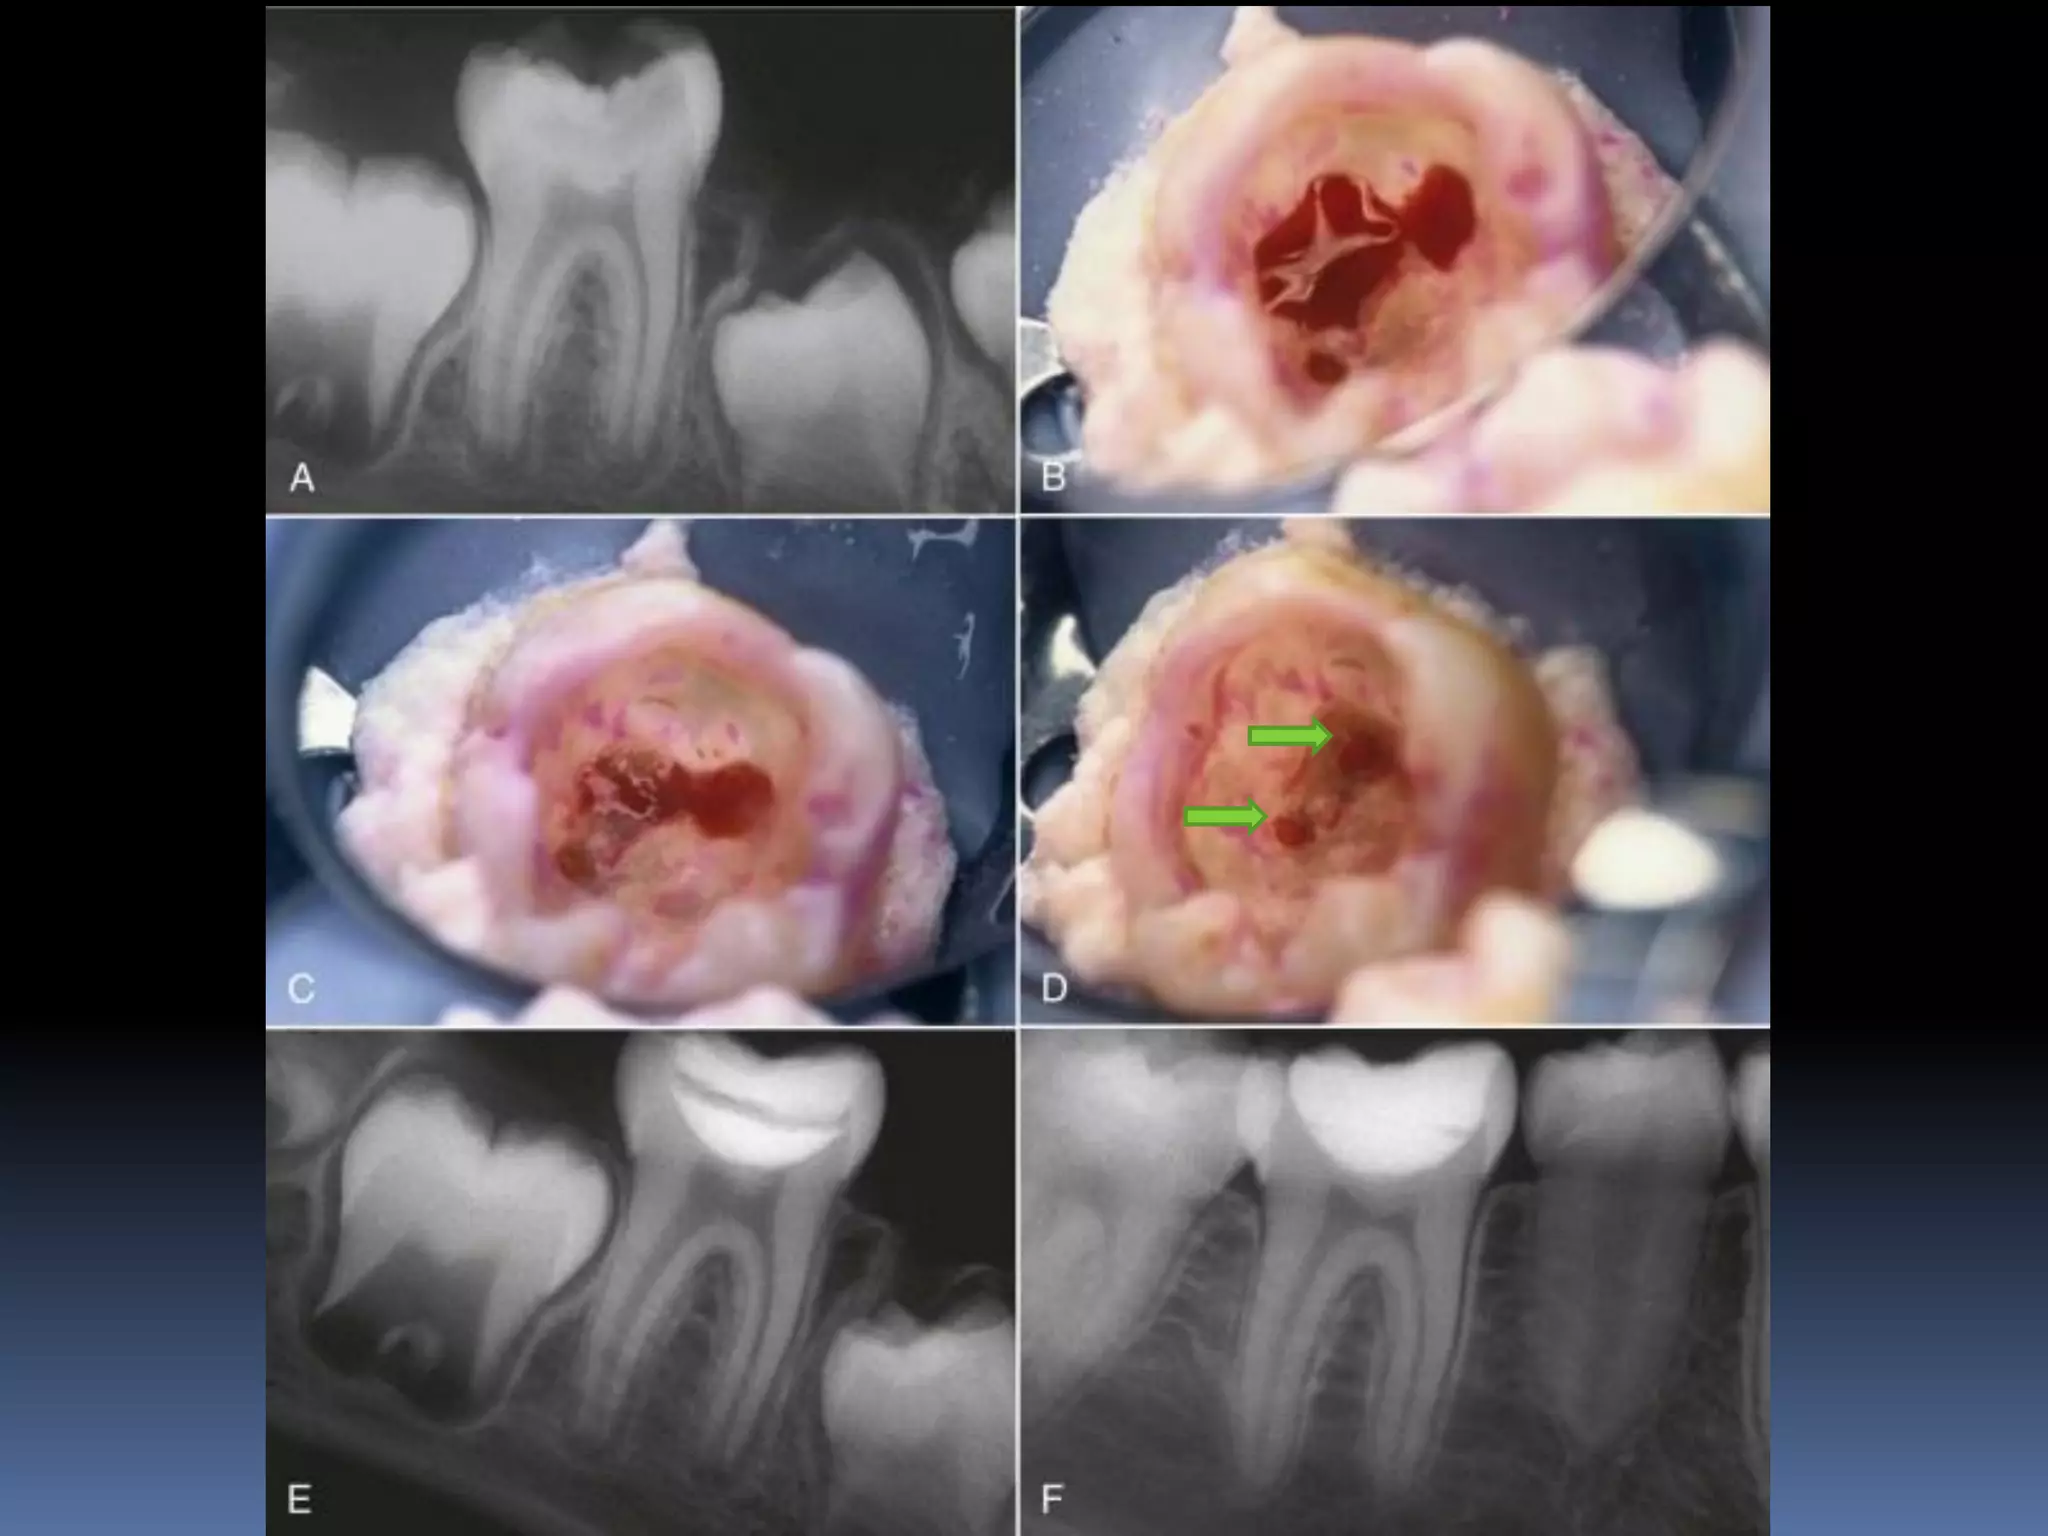

PULPOTOMY

The pulpotomy procedure involves removing only part of the

pulp, eliminating tissue that has inflammatory or degenerative

changes and leaving intact the underlying healthy pulp tissue

The surgical amputation of the coronal portion of an exposed

pulp to protect and preserve the remaining radicular pulp’s

vitality and function

Steps:

 All the carious dentin and pulp to the level of radicular

pulp are removed

- level of CEJ in anteriors

- level of canal orifices in posteriors

 Bleeding from the pulp stump is controlled with moist

cotton pellets and gentle pressure

 The chamber is rinsed with Sodium hypochloride

 The severed pulp is capped with

-

Calcium hydroxide

MTA

 This is then covered with Glass ionomer and the tooth is

restored with a restoration that seals completely

PULPOTOMY The pulpotomy procedureinvolves removing only part of the pulp, eliminating tissue that has inflammatory or degenerative changes and leaving intact the underlying healthy pulp tissue The surgical amputation of the coronal portion of an exposed pulp to protect and preserve the remaining radicular pulp’s vitality and function

Steps:  All thecarious dentin and pulp to the level of radicular pulp are removed - level of CEJ in anteriors - level of canal orifices in posteriors  Bleeding from the pulp stump is controlled with moist cotton pellets and gentle pressure  The chamber is rinsed with Sodium hypochloride  The severed pulp is capped with - Calcium hydroxide - MTA

 This isthen covered with Glass ionomer and the tooth is restored with a restoration that seals completely  Follow up • No signs of irreversible pulpitis • No radiographic signs of o internal resorption o external resorption o calcification o periapical radioluscency